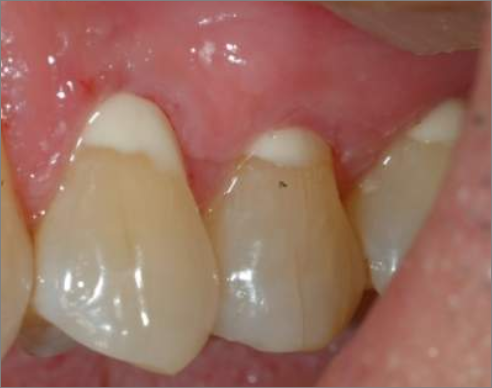

이 사진이 GI라는데,, 당연히 GI가 꺼려질 수밖에.. 그러나..